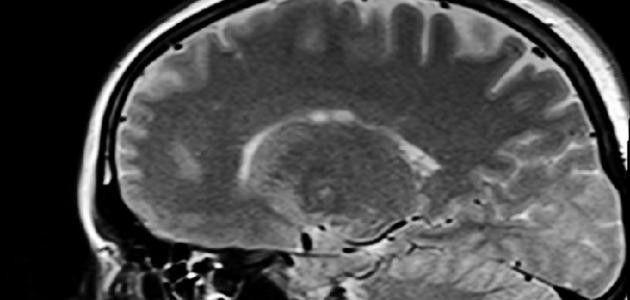

يُعتبر تشخيص نزيف المخّ صعباً ما لم يرتبط بظهور علامات تدلّ عليه، إذ يلجأ المختصّون لإجراء عدد من الفحوصات في حال ظهور بعض العلامات على المريض كفقدان الإحساس، وصعوبة الكلام، أو عند الاشتباه بوجود جلطة دماغية، ومن أبرز هذه الفحوصات ما يأتي:

- التصوير الطبقي المحوري (بالإنجليزية: Computed topography).

- التصوير بالرنين المغناطيسي (بالإنجليزية: Magnetic resonance imaging).